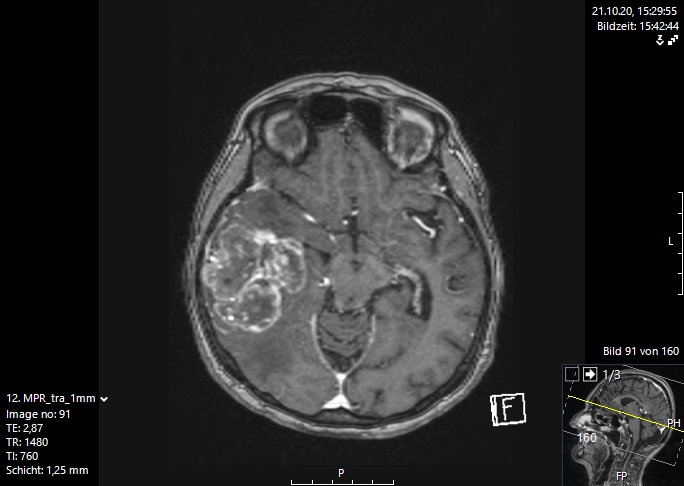

Η μαγνητική τομογραφία εγκεφάλου είναι η μέθοδος εκλογής για την απεικόνιση των εγκεφαλικών μεταστάσεων. Αυτή διενεργείται είτε επί υποψίας αλλοίωσης στο κεντρικό νευρικό σύστημα, λόγω ανάπτυξης μιας νευρολογικής συμπτωματολογίας ή απλά στα πλαίσια του γενικού staging με τακτικές απεικονίσεις στο σώμα και στον εγκέφαλο. Με τη βοήθεια αυτής της απεικονιστικής διαδικασίας μπορεί να γίνει ορατός ο παθολογικά αλλοιωμένος εγκεφαλικός ιστός με τις νεκρώσεις του καθώς και το περιεστιακό εγκεφαλικό οίδημα (συσσώρευση νερού στον εγκέφαλο).

Σήμερα υπάρχουν διάφορες διεγχειρητικές τεχνικές, που μας υποστηρίζουν στο στόχο μας, να αφαιρέσουμε όσο περισσότερο καρκινικό ιστό , αν γίνεται ιστό ακόμα και από την περιοχή γύρω από τον όγκο, που ονομάζουμε διηθητική ζώνη. Μερικές σύγχρονες διεγχειρητικές τεχνικές, είναι η νευροπαρακολούθηση, η νευροπλοήγηση με απεικόνιση των δεσμίδων, η ενδοσκοπική νευροχειρουργική και τα χειρουργεία με ασθενή σε εγρήγορση. Ο συνδυασμός λοιπόν ενός ασφαλούς χειρουργείου με ταυτόχρονη ολική αφαίρεση του όγκου αποτελεί τον στόχο της σύγχρονης χειρουργικής νευρο-ογκολογίας και στην περίπτωση των εγκεφαλικών μεταστάσεων. Οι εικόνες 1 και 2 απεικονίζουν μια ολική εξαίρεση μιας μετάστασης δεξιά κροταφικά. Αυτό είναι σαφέστατα πιο πιθανό να προσφερθεί από ειδήμονες νευροχειρουργούς (Gousias K, 2024) με ειδική εκπαίδευση σε μεγάλα κέντρα, μεγάλη χειρουργική εμπειρία και εξειδίκευση στην χειρουργική των όγκων καθώς και διεθνή αναγνώριση τους. Η επιτροπή Χειρουργικής Νευρο-ογκολογίας της Ευρωπαϊκής Νευροχειρουργικής Εταιρείας δημοσίευσε το προφίλ ενός expert χειρουργού για όγκους εγκεφάλου και νωτιαίου μυελού (Gousias K, 2024).